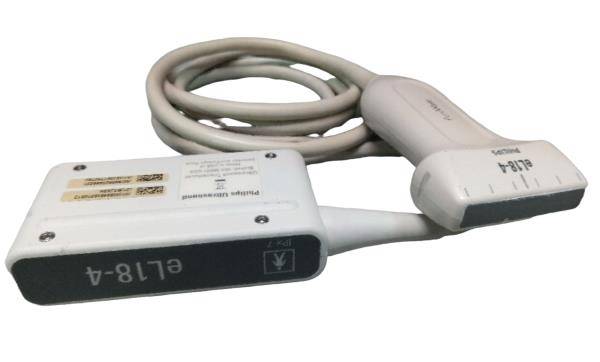

Versatile Probes for Comprehensive Diagnostics

The laptop ultrasound scanner comes with three types of probes: convex, linear, and transvaginal. These versatile probes make it suitable for various applications, whether it's obstetrics, gynecology, or general imaging. This versatility means clinicians can perform diverse examinations effectively, which is crucial for accurate diagnoses. So whether you're in a hospital or a private practice, this ultrasound scanner meets all your imaging needs.